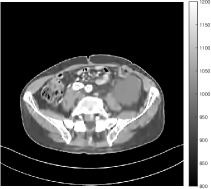

Figs. 8, 9, 10, and 11 show the reconstructions of the four independent slices using the FBP, PWLS-EP, PWLS-ST, PWLS-MARS2, PWLS-MARS3, PWLS-MARS5, and PWLS-MARS7 schemes, respectively. Additional Mayo Clinic experimental results of the parameter tuning case (Fig. 15) are shown in the supplementary document. Table 1 lists the RMSE and SSIM values of reconstructions of the four independent test slices, with the best values bolded. Generally, the five and seven layer models provided the best RMSE and SSIM values. They outperform the single-layer model by HU in RMSE on average. However, the MARS5 and MARS7 models perform similarly. In order to strengthen the benefits of the multi-layer model, Table 2 lists the RMSE of the reconstructions in four different ROIs (shown in the reference of Fig. 11) with seven methods for slice 100 of patient L506. By observing the reconstructed images, we see that although the ST model achieves a cleaner reconstruction result than FBP and PWLS-EP, it still sacrifices some sharpness of the central region and suffers from loss of details. The deeper models have a somewhat more positive effect in terms of maintaining subtle features, which is clearly more essential to clinical diagnosis. Furthermore, as we will discuss later, after considerable parameter tuning, we found that the information contained in residual maps is gradually decreased with the number of layers, eventually vanishing at some layer, which suggests that very deep unsupervised models might not offer significantly better image quality.

III.C.3. Analysis of Residual Maps

Here, we investigate the residual images over the layers of the MARS7 model. Fig. 12 displays the image reconstructed with MARS7 along with the residual images in different layers. The residual images are generated by applying the restoring operation to the corresponding columns of each residual matrix , forming images . Essentially, all the columns of are transformed into patches and accumulated back in the image to form the residual image in the th layer. We can observe that the residual images in the first three layers contain explicit structural information and we still find some delicate details in the fourth and fifth layers. However, we hardly see any valuable features in the residual images for the following layers, which is consistent with the fact that the transform is overwhelmed by noise in quite deep layers. Therefore, the ceiling for the potential of multi-layer sparsifying transform model may be 5 or 7 layers. The quantitive result also implies the same conclusion.